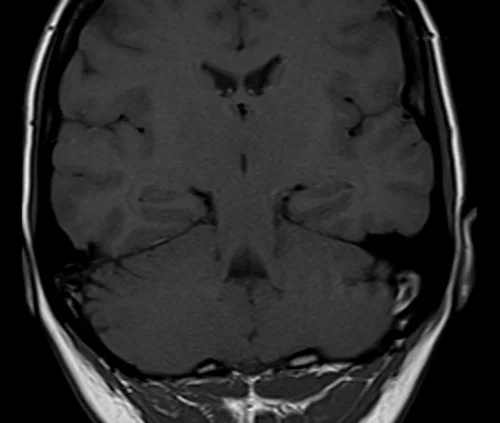

Brain epilipsy protocol mri coronal T1 images